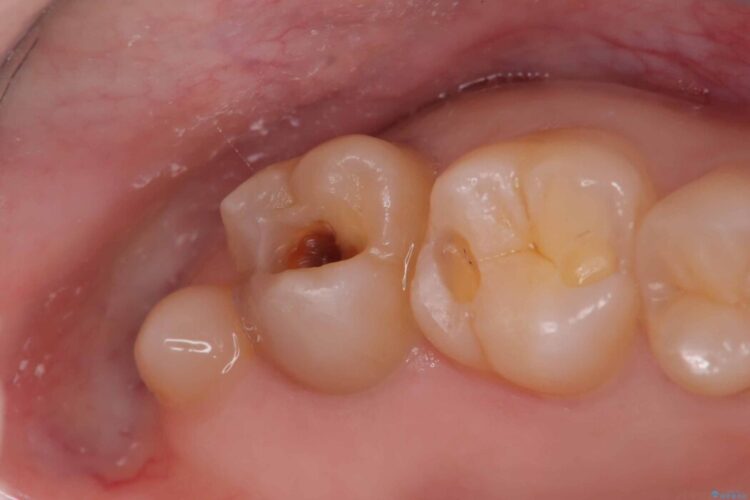

以前に詰めた白い詰め物の内部で、虫歯の再発が確認されました。

まずは古い詰め物と虫歯を丁寧に除去します。